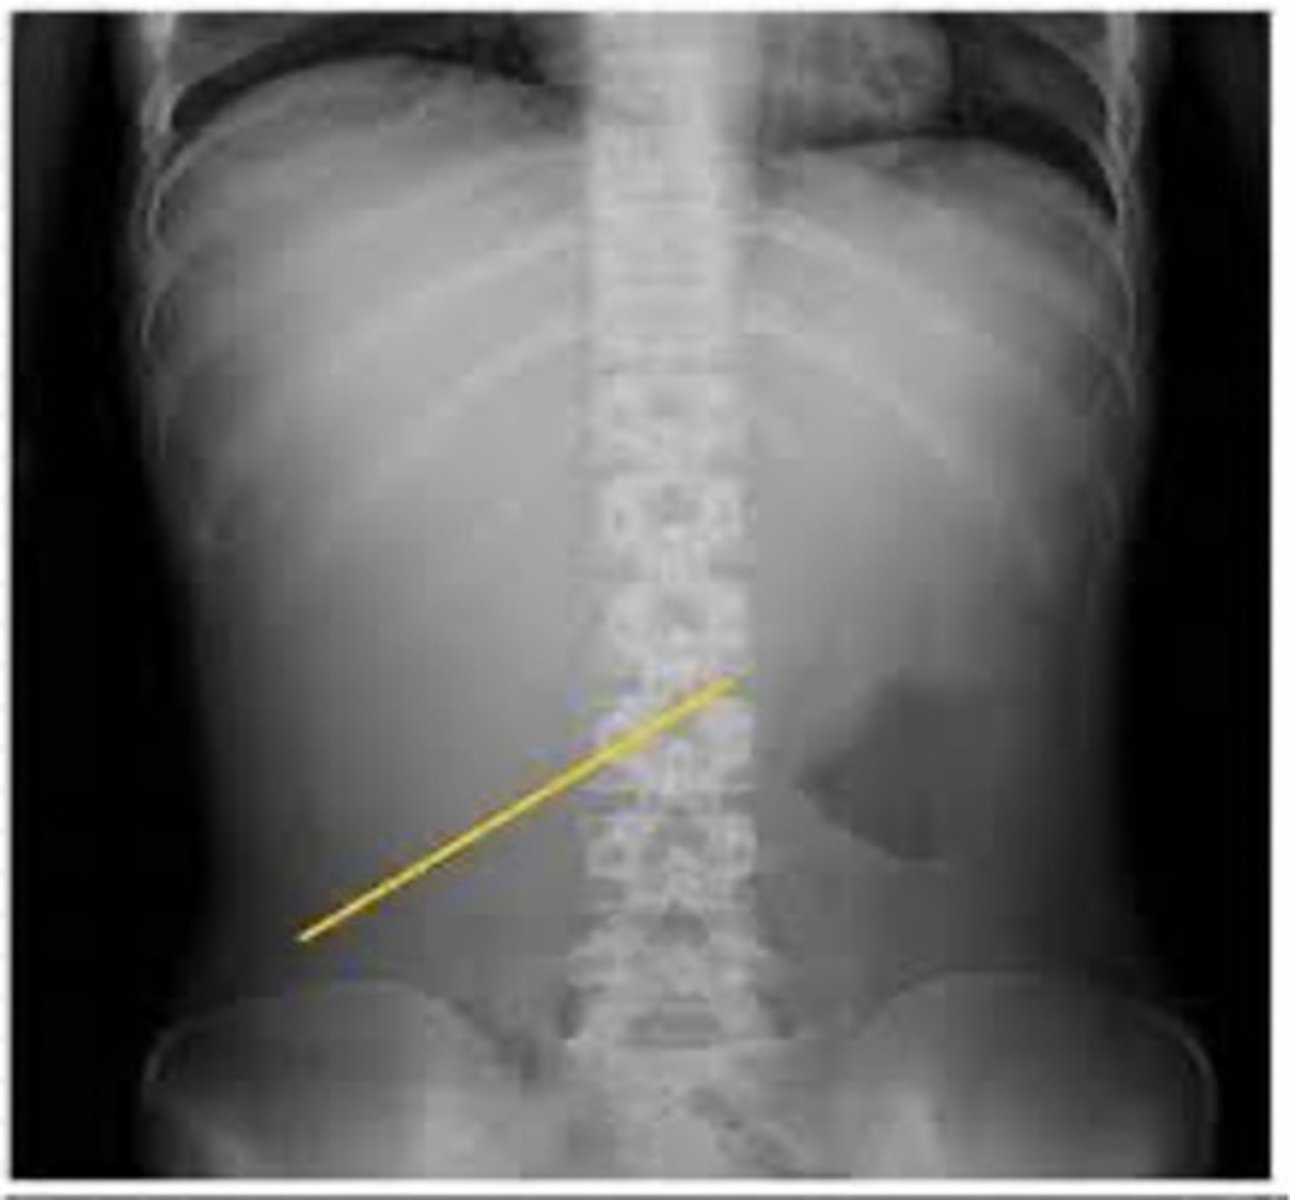

Abdominal aortic aneurysm calcification (pic 2)

Abdominal aortic aneurysm calcification (pic 3)